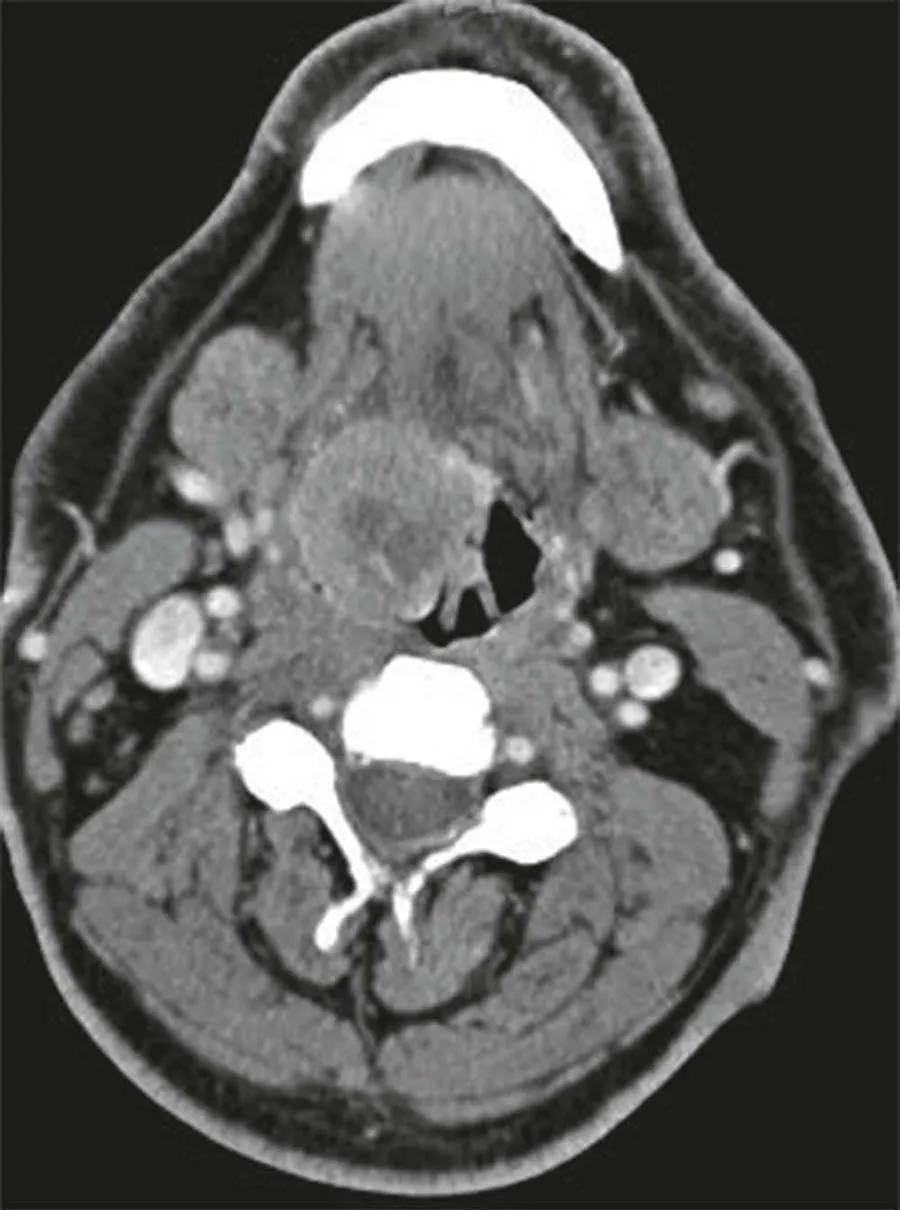

Incorporate today's most advanced imaging techniques with the new 4th edition of Head and Neck Imaging! A bestselling volume in the popular Case Review Series, this updated reference helps speed your differential diagnoses and ensure your proficiency, in addition to serving as a study guide for general radiology and neuroradiology subspecialty examinations, certificates of added qualification, and radiology/neuroradiology recertification. The all-inclusive volume can serve as a comprehensive review of the subspecialty and as a primer for excelling at the Head and Neck Tumor Boards.- Efficiently study and review with help from a format that mimics the General Diagnostic Radiology and Neuroradiology Board Exams. Each case begins with a differential diagnosis question and follows with multiple-choice questions, answers with rationale, and an emphasis on clinical issues.- Explore hot topics including CT and MR angiography of the neck; multi-detector CT with 3D reconstructions; post-transplant lymphoproliferative disorders; HIV infections; squamous cell carcinoma, diagnostic and therapeutic image-guided procedures; medical economics; and much more.- Master the latest techniques with 150 new and 50 updated head and neck cases and over 800 images focusing on differential diagnosis, tumor staging, treatment options, and resectability issues.- Enhance your understanding with multiple-choice questions accompanying each case, emphasizing cranial nerves, skull base lesions, sinonasal, orbital, salivary gland, aerodigestive system mucosal lesions and deep space neck masses.- Utilize convenient cross-references to recent articles.- Stay abreast of the most recent discoveries in HPV (+) squamous cell cancers, high-resolution imaging, and CTA, MRA, and CISS applications.- Explore the differential diagnosis and/or anatomic details of every case presented.- Understand the surgical and radiation therapy considerations for cosmetic and functional outcomes.- Expert Consult eBook version included with purchase. This enhanced eBook experience allows you to search all of the text, figures, and references from the book on a variety of devices.